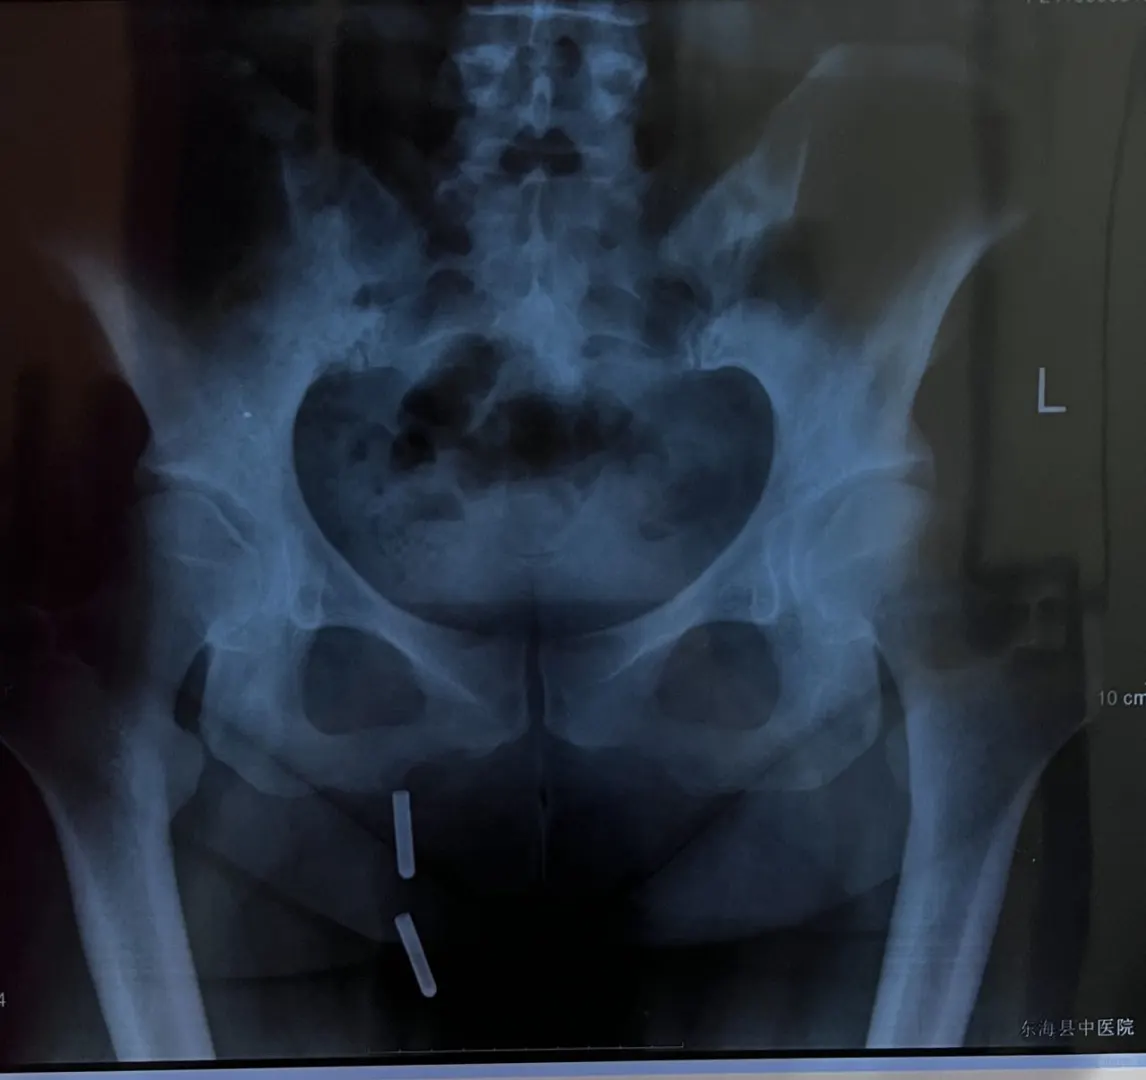

产后8个月宝妈 剖腹产 核心没有力量 骨盆散 坐着的时候脊椎非常累 脊椎僵硬 蹲不下 初步判断 剖腹产横剖刀疤 导致气血很难入小腹 晚上手脚容易热 小腹凉的 睡眠不好 气血不入小腹 气血不归元所以睡眠难好 给她调整刀做松解 并且把任脉调整 并用五年陈野生艾灸之 初始手开始凉 小腹开始暖和 气血归元开始 随着艾灸的补气 慢慢小腹后腰越来越暖 手脚也开始热 上午结束后感觉小腹饱满 坐着的时候骨盆感觉能立起来了 其实是身体前侧能发力了 脏腑提升与胸腹的空间打开 呼吸自然能入盆腔 起来那种骨盆向前顶的感觉就弱了 感觉到从耻骨那里向上能顶上力了 调整过后从工作室走到医院取片子 再从医院走到酒店总共走2公里 对于原来的她来说是不敢想像的 下午有针调臀部肌肉与骨骼配合艾灸 调整之前臀部肌肉是囊的没有力量 调整过后臀部肌肉明显感觉 再测试坐起来骨盆立的更好 起来走路股骨头滑动更好 而且走的时候可以看出臀大肌能发力了 初来时候臀部整个是僵的 从她的片子上也能看出来 坐骨到大转子的距离特别小 骨盆后倾坐骨外开 这样她的股骨头就卡在髋臼的前上方 所以会导致她蹲不下去 因为股骨头卡住了 股骨头在臼窝里的滑动弱了 所以造成不好蹲下 通过一系列调整 股骨头在臼窝里的活动空间变大 所以就能蹲得下去了 今天的调整案主觉得很满意 我看她下蹲的照片 明天再帮她调整一下髌骨 以及脚踝 她可以蹲得更深 让她练习盆底肌收缩 她说感觉更有力量了